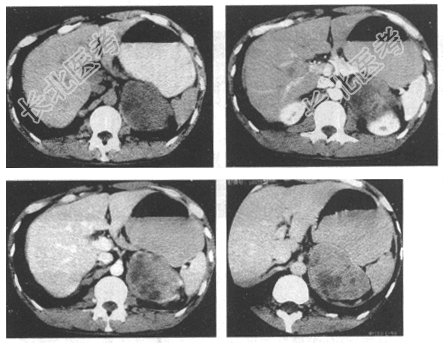

- [材料题] 患者,男,43岁。体检发现左肾上腺肿物4天。患者4天前B超发现左中上腹肿物,边界尚清,形态欠规则,不伴头痛、头晕,不伴心悸、视物模糊。查体:BP 111/66mmHg。

- 简答题1、CT检查如下图,请问拟诊断为什么?